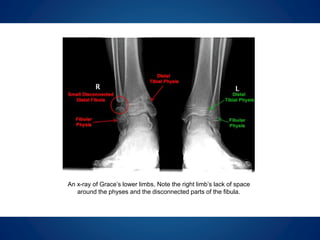

An x-ray of Grace’s lower limbs. Note the right limb’s lack of space

around the physes and the disconnected parts of the fibula.

During our first appointment, I examined

Grace and reviewed her medical films. I

found that her physis seemed to have

stopped growing and as a result of her

previous surgeries, there was only a small

distal fibula remaining near her ankle and it

was not attached to the rest of her fibula.

I was concerned that this small amount of

bone would be insufficient to buttress and

protect her ankle. In addition, the ankle was

bowing (varus) and surgery would become a

necessity if it continued to drift into a more

varus position.